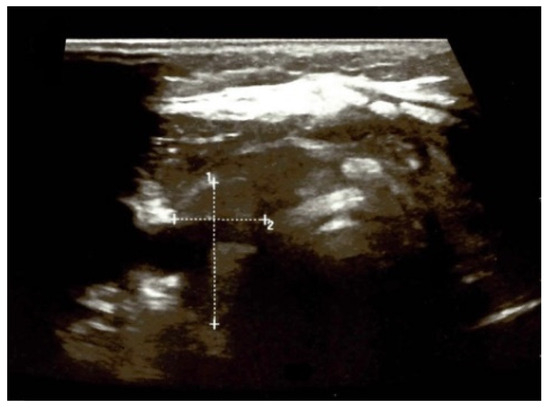

4.1.1. First Admission

4.1.2. Initial Thyroidectomy and Removal of the Ectopic Thyroid Tissue